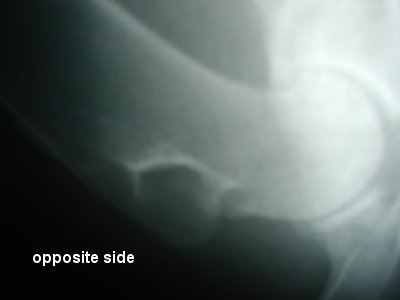

| ladyR, Great Dane, F, 123 lb, 10yo, 37", RAW diet, Spondylosis |

| So far: Vet #1 - osteosarcoma Vet #2 - arthritic changes Vet #3 - Arthritic changes Jan 2004 - Board Certified Radiologist - Arthritic changes |

| There are

only 2 xrays, I used the zoom on the camera to get the below different views |